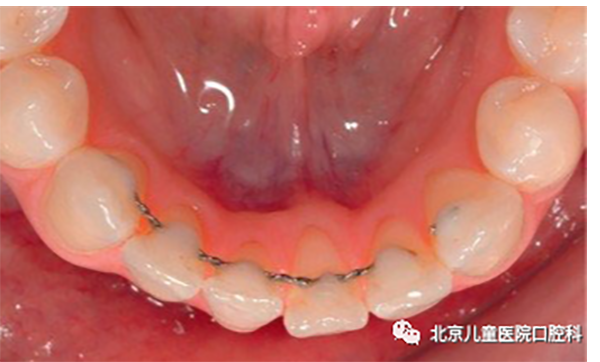

多为粘接于牙齿舌面的舌侧丝保持器。常用于下切牙拥挤解除后需要永久保持的成年患者。